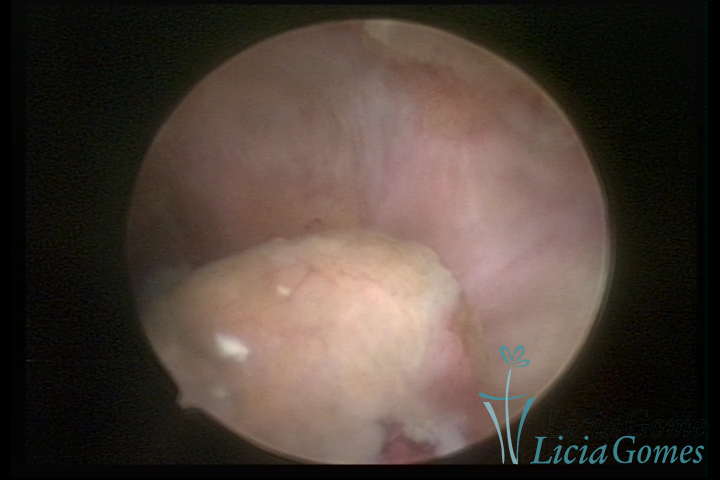

Este pode apresentar uma gama variável de aspectos macroscópicos, com aspecto pseudopolipoide; lembrando tecido cerebroide ou com reação deciduoide;a vascularização superficial é mais evidente e com vasos em formatos de saca-rolha ou espirais visualizando também a vascularização com atípias, com aumento do calibre dos vasos superficiais, pode ser encontrado também tecido em necrose, poderá haver um pequenos dendritos (papilomatoso).